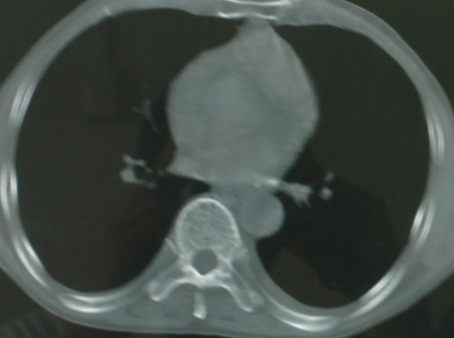

以下是引用医影拾贝在2008-6-3 18:48:00的发言:[br]双上肺弥漫性小结节影,纵隔窗内钙化淋巴结影,考虑血播性tb可能性较大,不除外肺ca可能

以下是引用卜一在2008-6-3 19:33:00的发言:[br]双肺结节,以双上肺分布为多,期间搀杂片状致密影及索条致密影。考虑:继发性肺结核伴血型播散可能性大。不除外肺泡ca的可能!另:椎体退变!

以下是引用panyishengct在2008-6-3 21:09:00的发言:[br]双上肺弥漫性小结节影,纵隔窗内钙化淋巴结影,考虑矽肺或/和tb可能性较大,不除外肺ca可能。腰椎考虑退变。 [br][br]